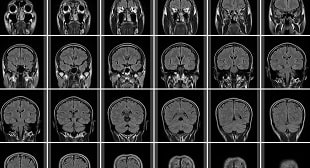

脳転移が起こると余命6半年以内と推定